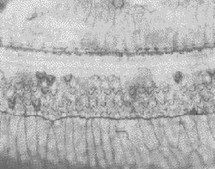

毛细胞白血病

毛细胞白血病(hairycellleukemia,HCL)很少见B淋巴细胞肿瘤常...